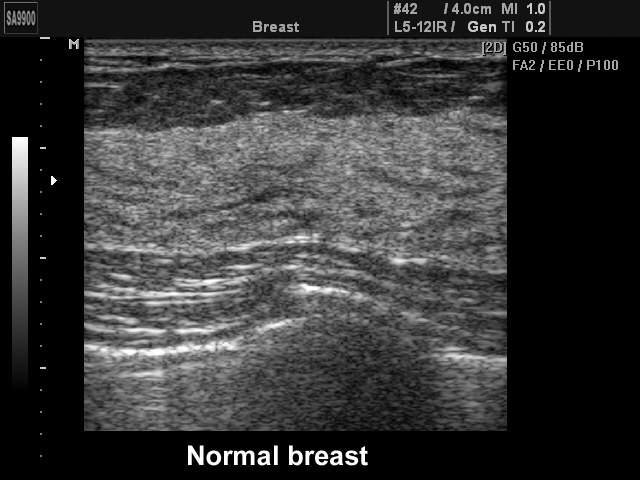

Breast - norm, B-mode

Breast - norm, B-mode (echogramm №220)

[RU] Ultrasound image №220: Breast (norm) in B-mode.

Echogramm was received by ultrasound scanner SonoAce-9900 (out of production).